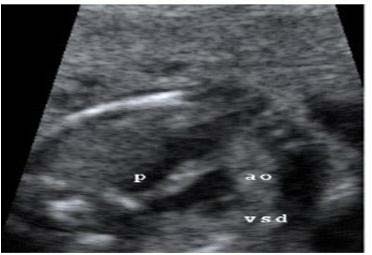

Una paciente gestante de 23 semanas con sospecha de malformación cardiaca fetal congénita fue derivada al servicio de cardiología pediátrica. Se realizó una ecocardiografía fetal, diagnosticándose un arco aórtico derecho mediante el plano de Yagel: tres vasos- tráquea. (Figura 1)

Figura 1. Ecocardiografía Fetal